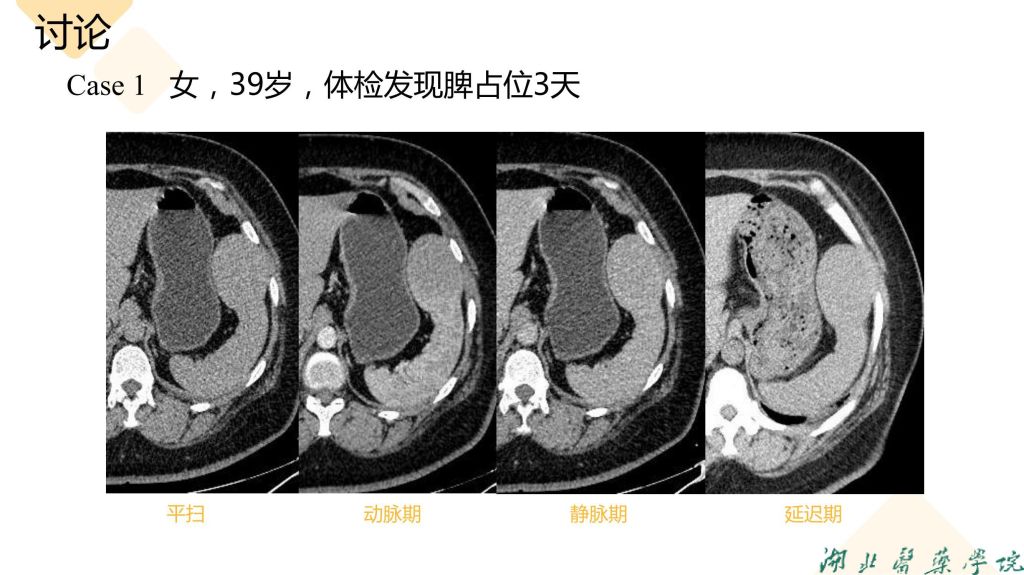

病例分享-脾脏实质性占位性病变